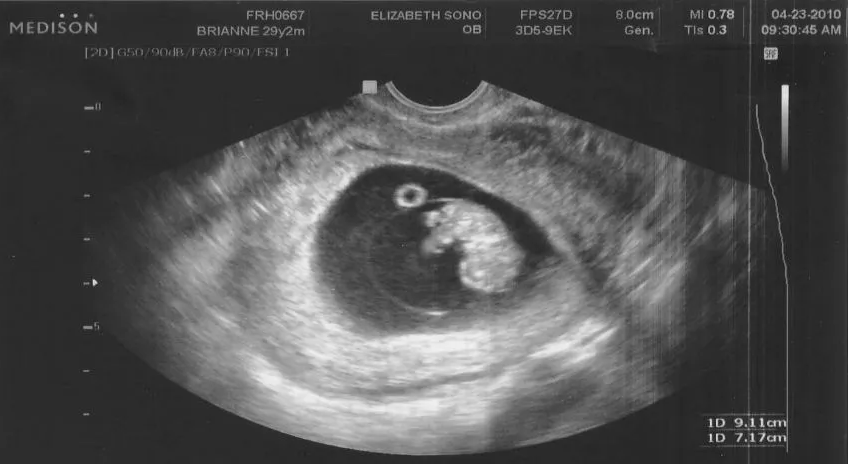

Ещё в 1993 году ученые биологического факультета МГУ, которых трудно заподозрить в особой религиозности, сделали официальное заявление, согласно которому с биологической точки зрения эмбрион становится человеком с первой секунды зачатия.

Фото УЗИ.